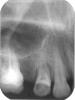

ИринаИ Опубликовано 13 февраля, 2007 Поделиться Опубликовано 13 февраля, 2007 Многоуважаемые профессионалы! Пожалуйста, не откажите посмотреть прилагаемые снимки и помочь с диагнозом. Сейчас я имею их 3 - и проблема в том, что они взаимоисключающие в отношении тактики лечения. Мне 46 лет. Располагаю только 18ю зубами. Каждый уже дорог. Т.к. появились проблемы с ВНЧС, 2 недели назад обратилась к врачу , чтобы санировать зубы перед протезированием, и, как мне свойственно, с ходу вляпалась в проблему.Речь о зубе, с которого мы с врачом начали – 24м. Была старая пломба (снимок 01 – до начала лечения), начали снимать – боль, вскрыта пульпарная камера, пройдены 2 канала, поставлен каласепт. Диагноз врача – периодонтит, хронический, м.б. и травматический ( на зубок шла основная нагрузка , тк у него – редкий случай в моем беззубом рту!-есть антагонист ). В течение недели – боль, почти постоянная, резкая при надавливании и накусывании , особенно со стороны «внутренней» стороны коронки зуба. В этот момент- см. снимки «на каласепте»02 и 03. Открыт зуб, расширены каналы, они «чистые», пройдены до конца. Поставлены турунды(так-?) с рокалем. Ибупрофен 400мг 3 р в день 4 дня. Через 6 дней боль вроде утихла, но в течении недели была небольшая припухлость над зубом на уровне крыла носа. Но – когда я обратилась на всякий случай за консультацию к парадонтологу, -та задумалась над снимками, позвала хирурга- имплантолога и они вместе констатировали: «24 зуб под временной пломбой. Перкуссия безболезненна. При пальпации подвижность дистальной стенки.»поставили диагноз: «24 зуб- …в нижней трети корня неравномерный перелом( горизонтально).Рекомендовано удаление 24 зуба . С пародонтитом изменения в костной ткани не связаны». Мой врач-терапевт не видит перелома. (Увы, она работает в частном кабинете без рентгена и я ношу ей снимки из клиники, в к-рой увидели перелом). Сегодня сделала еще 2 снимка «на рокале» 04,05.Не хочу остаться беззубой старушонкой!!!!!-тк ещё и 26й, плохо, как оказалось, запломбированный 10 лет назад уже со свищом – на удаление, так? Обратилась сегодня ещё к 3м хирургам, предъявила зуб и снимки – один говорит –не вижу перелома, но есть большая гранулема(!), не вылечить. Два других не видят перелома, предлагают пробовать лечить, но сомневаются в успехе из-за «большой резорбции костной ткани—так?- могу переврать). Все доктора, кроме «гранулёмщика» производят впечатление профессионалов, и я в смятении.Так есть перелом или нет???То есть- Лечить или не лечить, а удалять??? И если удалять, то какой в первую очередь – 24 или 26? Пожалуйста, откликнитесь. Старалась писать сухо и по делу, но очень переживаю, т.к. 10 лет назад на этой стороне лица после стоматологического лечения у меня в течение 1,5 лет были зубные боли, причину которых не смогли уверенно определить, и, ясно дело, постфактум лечили уже соматизированную депрессию. Это был трудный опыт выживания, и зря травмировать эту часть лица я очень, очень боюсь. Спасибо.Ирина. Ссылка на комментарий

Skip Опубликовано 13 февраля, 2007 Поделиться Опубликовано 13 февраля, 2007 Многоуважаемые профессионалы! Пожалуйста, не откажите посмотреть прилагаемые снимки и помочь с диагнозом. Сейчас я имею их 3 - и проблема в том, что они взаимоисключающие в отношении тактики лечения. Мне 46 лет. Располагаю только 18ю зубами. Каждый уже дорог. Т.к. появились проблемы с ВНЧС, 2 недели назад обратилась к врачу , чтобы санировать зубы перед протезированием, и, как мне свойственно, с ходу вляпалась в проблему. Речь о зубе, с которого мы с врачом начали – 24м. Была старая пломба (снимок 01 – до начала лечения), начали снимать – боль, вскрыта пульпарная камера, пройдены 2 канала, поставлен каласепт. Диагноз врача – периодонтит, хронический, м.б. и травматический ( на зубок шла основная нагрузка , тк у него – редкий случай в моем беззубом рту!-есть антагонист ). В течение недели – боль, почти постоянная, резкая при надавливании и накусывании , особенно со стороны «внутренней» стороны коронки зуба. В этот момент- см. снимки «на каласепте»02 и 03. Открыт зуб, расширены каналы, они «чистые», пройдены до конца. Поставлены турунды(так-?) с рокалем. Ибупрофен 400мг 3 р в день 4 дня. Через 6 дней боль вроде утихла, но в течении недели была небольшая припухлость над зубом на уровне крыла носа. Но – когда я обратилась на всякий случай за консультацию к парадонтологу, -та задумалась над снимками, позвала хирурга- имплантолога и они вместе констатировали: «24 зуб под временной пломбой. Перкуссия безболезненна. При пальпации подвижность дистальной стенки.»поставили диагноз: «24 зуб- …в нижней трети корня неравномерный перелом( горизонтально).Рекомендовано удаление 24 зуба . С пародонтитом изменения в костной ткани не связаны». Мой врач-терапевт не видит перелома. (Увы, она работает в частном кабинете без рентгена и я ношу ей снимки из клиники, в к-рой увидели перелом). Сегодня сделала еще 2 снимка «на рокале» 04,05.Не хочу остаться беззубой старушонкой!!!!!-тк ещё и 26й, плохо, как оказалось, запломбированный 10 лет назад уже со свищом – на удаление, так? Обратилась сегодня ещё к 3м хирургам, предъявила зуб и снимки – один говорит –не вижу перелома, но есть большая гранулема(!), не вылечить. Два других не видят перелома, предлагают пробовать лечить, но сомневаются в успехе из-за «большой резорбции костной ткани—так?- могу переврать). Все доктора, кроме «гранулёмщика» производят впечатление профессионалов, и я в смятении. Так есть перелом или нет??? То есть- Лечить или не лечить, а удалять??? И если удалять, то какой в первую очередь – 24 или 26? Пожалуйста, откликнитесь. Старалась писать сухо и по делу, но очень переживаю, т.к. 10 лет назад на этой стороне лица после стоматологического лечения у меня в течение 1,5 лет были зубные боли, причину которых не смогли уверенно определить, и, ясно дело, постфактум лечили уже соматизированную депрессию. Это был трудный опыт выживания, и зря травмировать эту часть лица я очень, очень боюсь. Спасибо.Ирина. Здравствуйте, Ирина. Ситуация достаточно сложная и для того, чтобы дать объективную оценку Вашего случая, необходима конечно же очная встреча... Но, попытка не пытка, может быть мы здесь сообща и попытаемся хоть что-нибуть прояснить. Сначала несколько вопросов: 1. На момент обращения к врачу зуб 24 уже болел? Если да, то опишите характер болей(от температуры, при надавливании, самопроизвольно...) 2. Во время лечения, Ваш врач использовал какой-нибудь электронный прибор для определения длинны канала (т.н. апекслокатор) или ограничивался только тактильным чувством? На снимках сложно что-либо разобрать, но настораживает подвижность части зуба, которую определил хирург. Может быть это и перелом, т.к. в устьевой части и верхней трети каналов, как мне кажется по снимкам, изрядно поработали бором, что могло привести и к перфорации стенки канала. Кистогранулёмы я не нашёл, но вот на одном участке поверхности корня, ближе к коронке зуба и обрщённого к клыку, предположительно имеет место ограниченная резорбция корня (рассасывание). Совет на будущее. Зубы старайтесь лечить там, где есть возможность сделать рентген, т.к. делать это приходиться непосредственно во время лечения... Ссылка на комментарий

NataLee Опубликовано 15 февраля, 2007 Поделиться Опубликовано 15 февраля, 2007 Про этику: есть такое заболевание, свойственное гуманитариям, "низкая культура отказа" называется. Т.е. излишняя, глупая деликатность. Да, маразм. Да, умом понимаешь, что здоровье дороже, но обидеть своего многолетнего врача недоверием просто не получается, язык не поворачивается. И, к тому же, повторяю: в немолодые свои уже годы все ещё не нашла я врача в г. СПб. На вашем сайте был такой совет: всех расспрашивать. Я всегда так и делала. И парадокс: вроде врачей много, но и неприкаянных пациентов, не знающих кому можно довериться- море. Все вокруг вздыхают, что надо к стоматологу, но никто не знает, какая у них репутация и боятся! Особенно старичье со своим опытом общения с советской стоматологией. Ответьте, пожалуйста мне на вопрос: с переломом можно жить, потянув с удалением или это опасно?? Т.е. такой детский страх- не будет ли страшного-страшного -страшного воспаления, не опасно ли это для соседнего зуба?Сейчас мой врач понесла снимки на консультацию к какому-то специалисту, и только в понедельник (через 4 дня то есть) сообщит мне его мнение.Ирина. Здравствуйте! Немного поздно включаюсь в дискуссию, но всё-таки выскажу своё мнение. Мне кажется (судя по клинике и снимкам), перелом ЕСТЬ. Возможно, вертикальный. Жить с ним можно какое-то время, но сломанный зуб использовать для протезирования, как опорный - нельзя. Кончается это всё равно удалением. Страшного-страшного воспаления может и не быть, как правило, перелом проявляет себя болью, подвижностью зуба, часто появляется свищ. Не могу судить, не видя ситуации лично - но мне кажется, зуб этот придётся всё же удалить и искать какое-то другое решение проблемы - имплантация либо изменение плана протезирования. Ну не нравится мне этот зуб, интуиция говорит, что не ладный он... Ссылка на комментарий